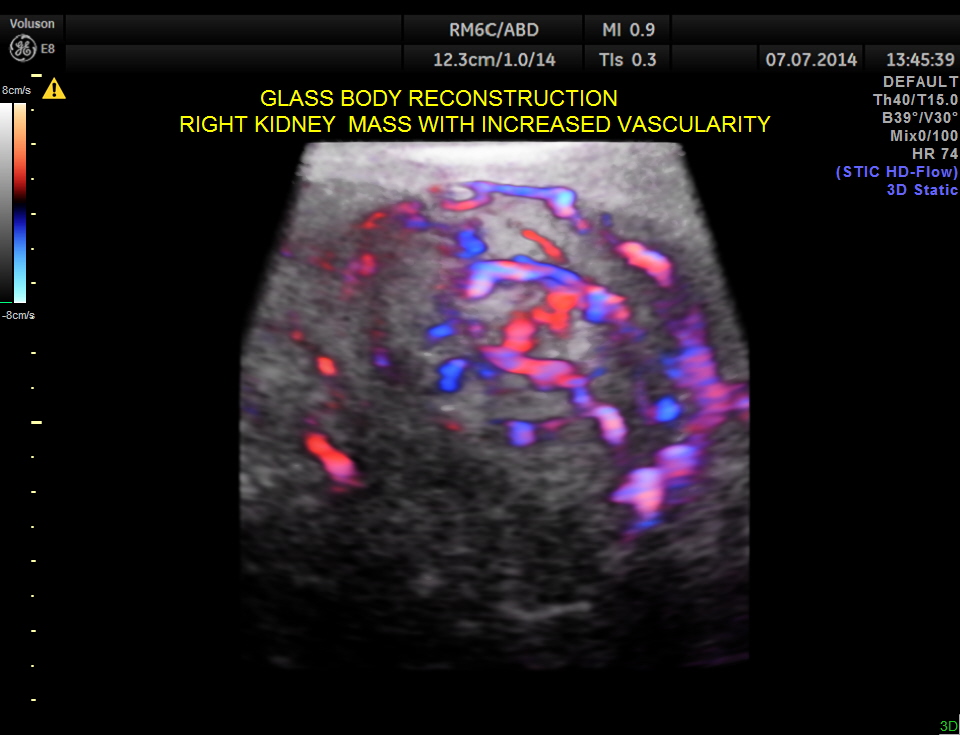

GLASS BODY RECONSTRUCTION shows increased vascularity.

In this patient the increased vascularity is brought out very well by glass body imaging . Clots of blood seen in the urinary bladder gave the false impression of a mass lesion in the bladder initially.The importance of a dynamic study of turning the patient to the sides should always be remembered.